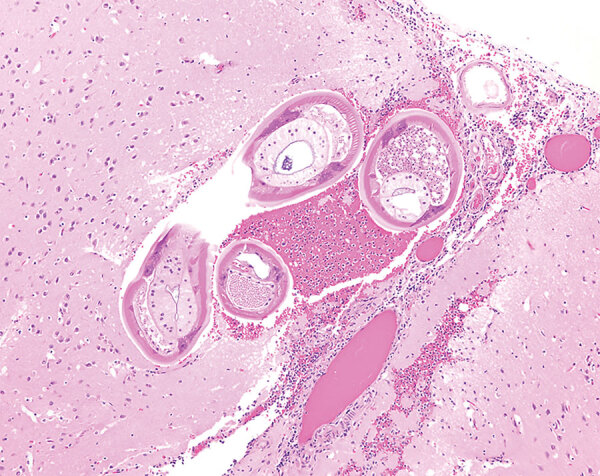

Angiostrongylus cantonensis in a Red Ruffed Lemur at a Zoo, Louisiana, USA

Description:A red ruffed lemur (Varecia rubra) from a zoo in Louisiana, USA, was euthanized for worsening paresis. Brain and spinal cord histology identified eosinophilic meningoencephalomyelitis with intralesional adult Angiostrongylus sp. nematodes. PCR and sequencing confirmed A. cantonensis infection, indicating this parasite constitutes an emerging zoonosis in the southeastern United States.